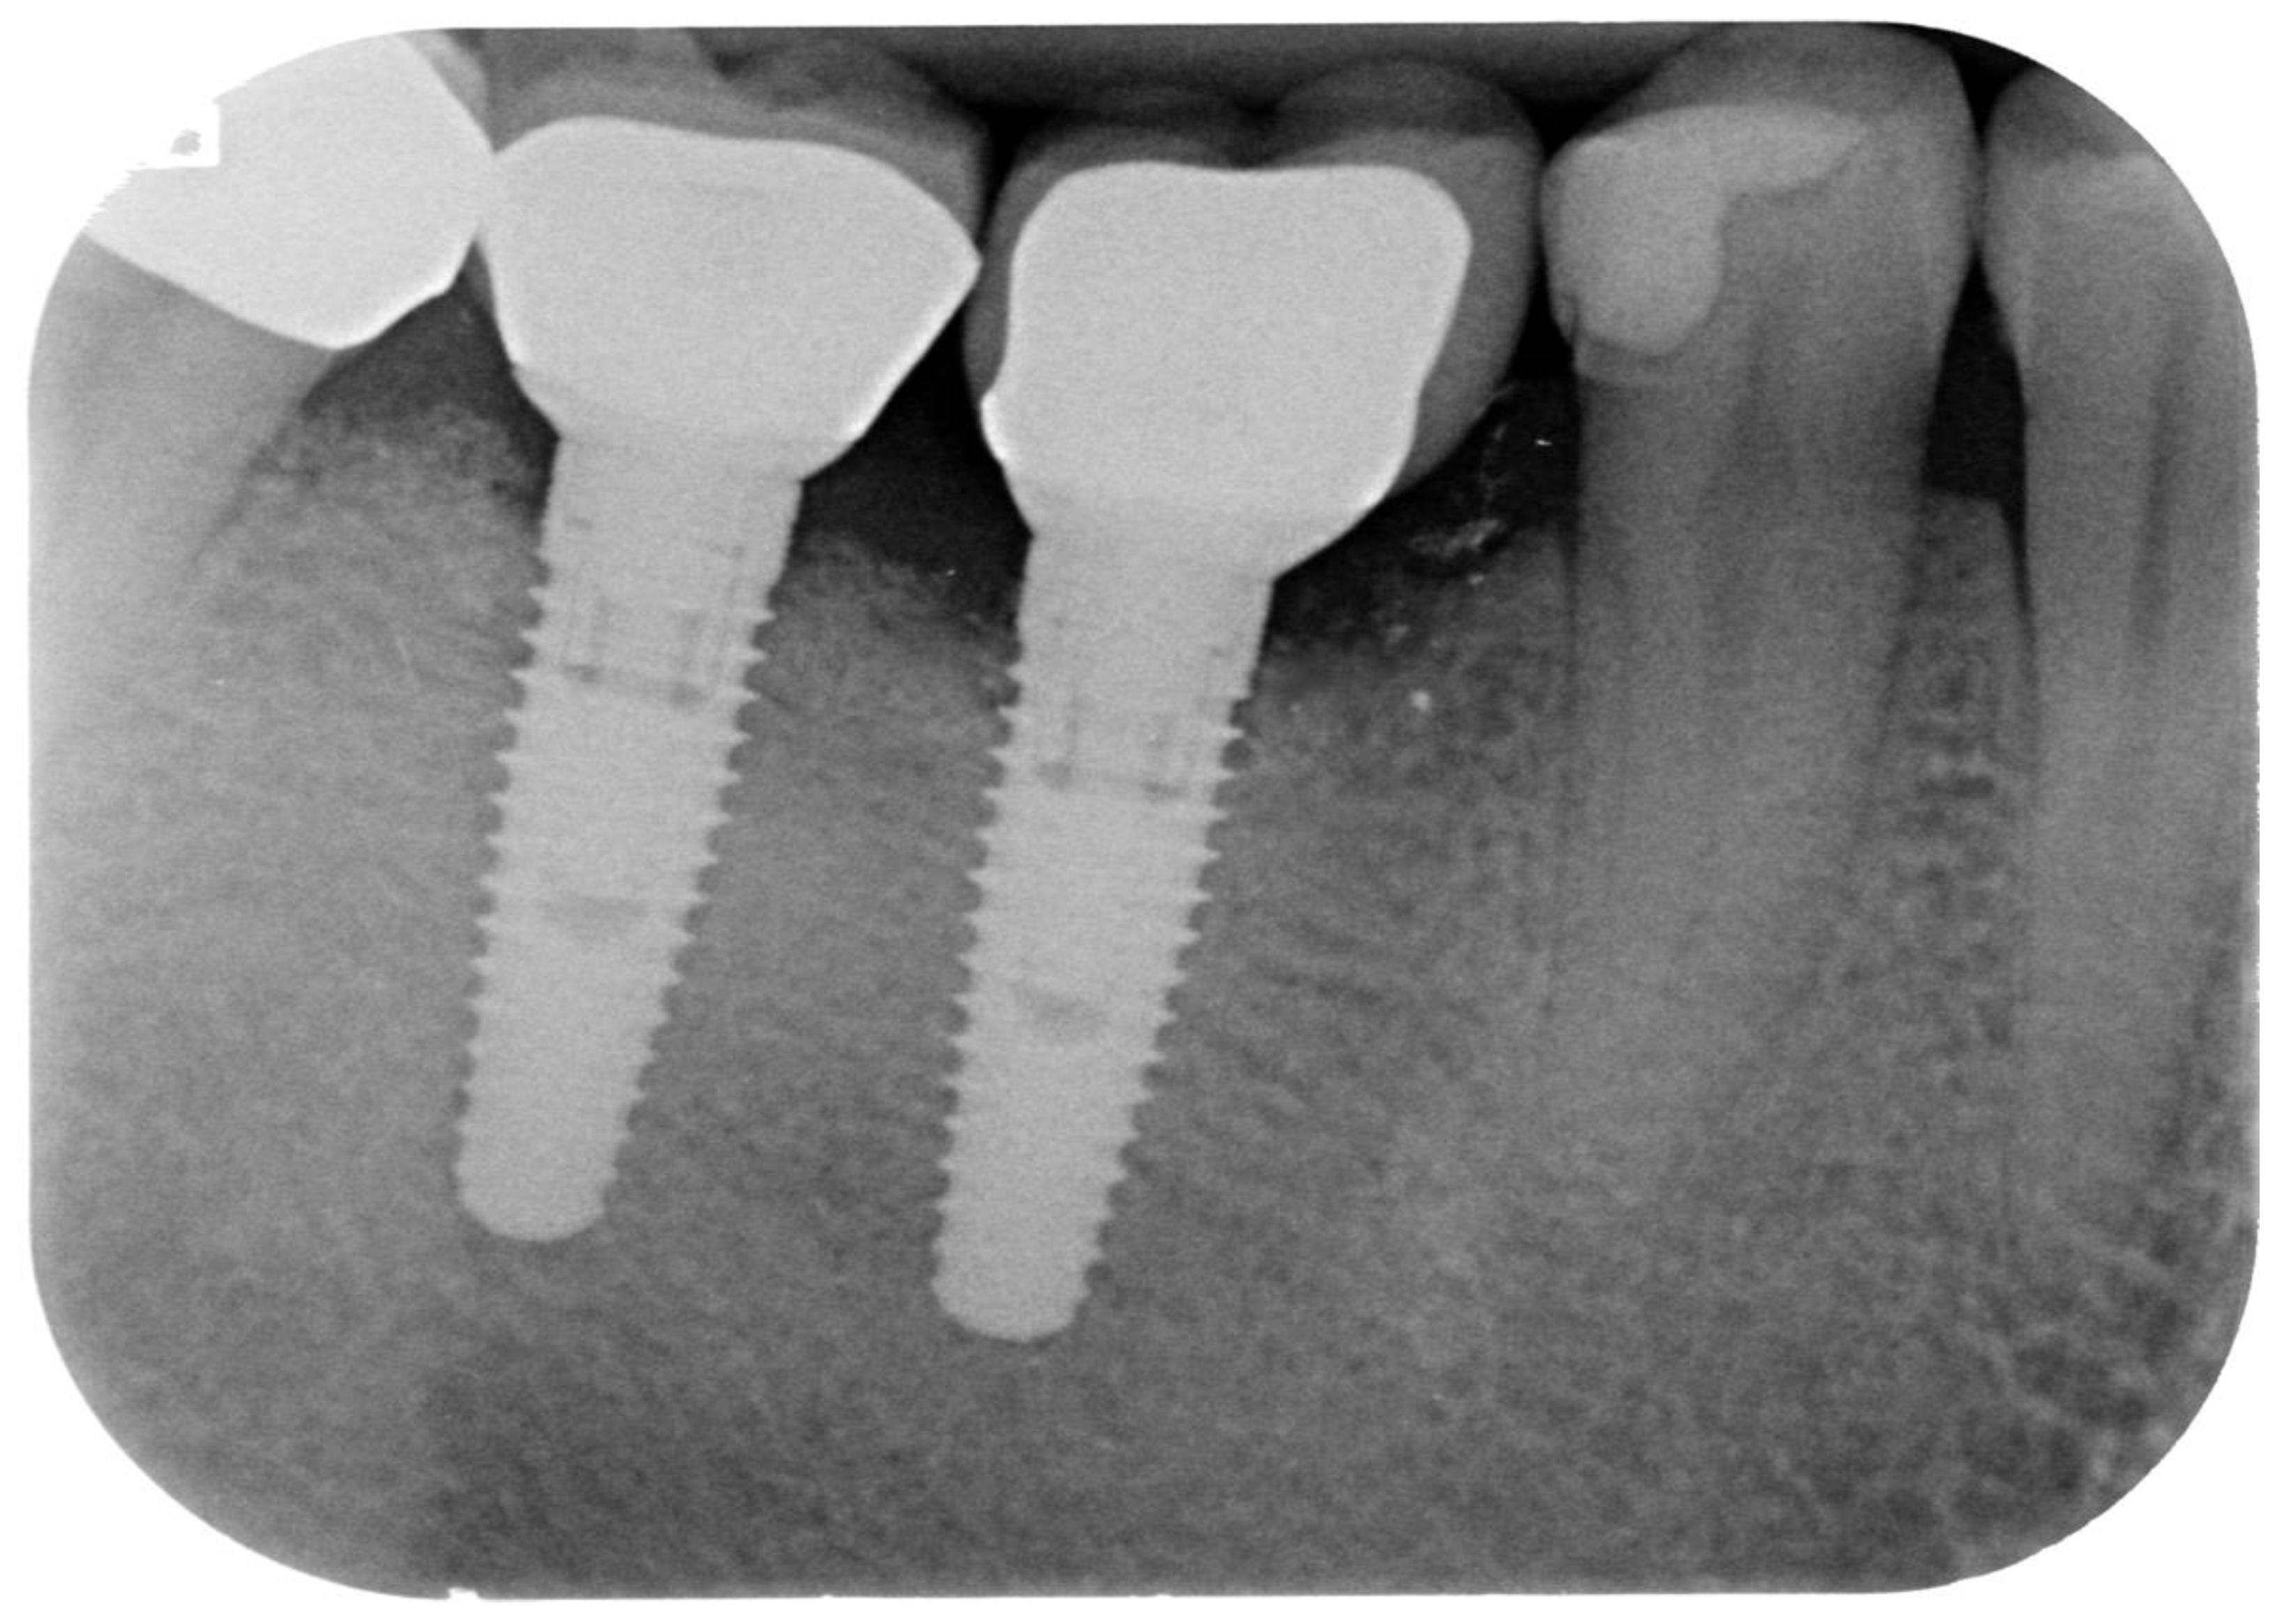

Peri-Implantitis: Application of a Protocol for the Regeneration of Deep Osseous Defects. A Retrospective Case Series

2. Materials and Methods